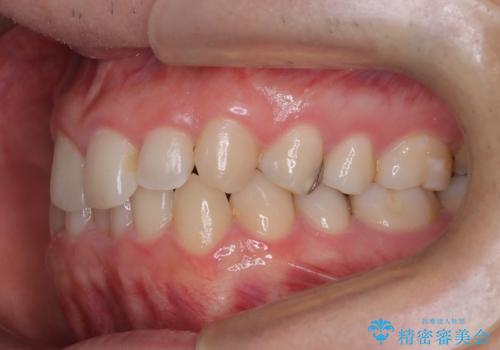

- 下の歯のがたつき(叢生)、真ん中(正中)が右にずれていることを主訴に来院されました。右上前から3番目の永久歯が埋まっている(埋伏)していることから正中は可能な限り合わせることをゴールとしてマウスピースでの矯正治療を選択しました。

今回の矯正治療では、透明なマウスピース型の装置インビザラインを使用しました。がたつきをとるため、安全性が確保できる範囲で歯と歯の間を少し削り必要なスペースを確保しました。